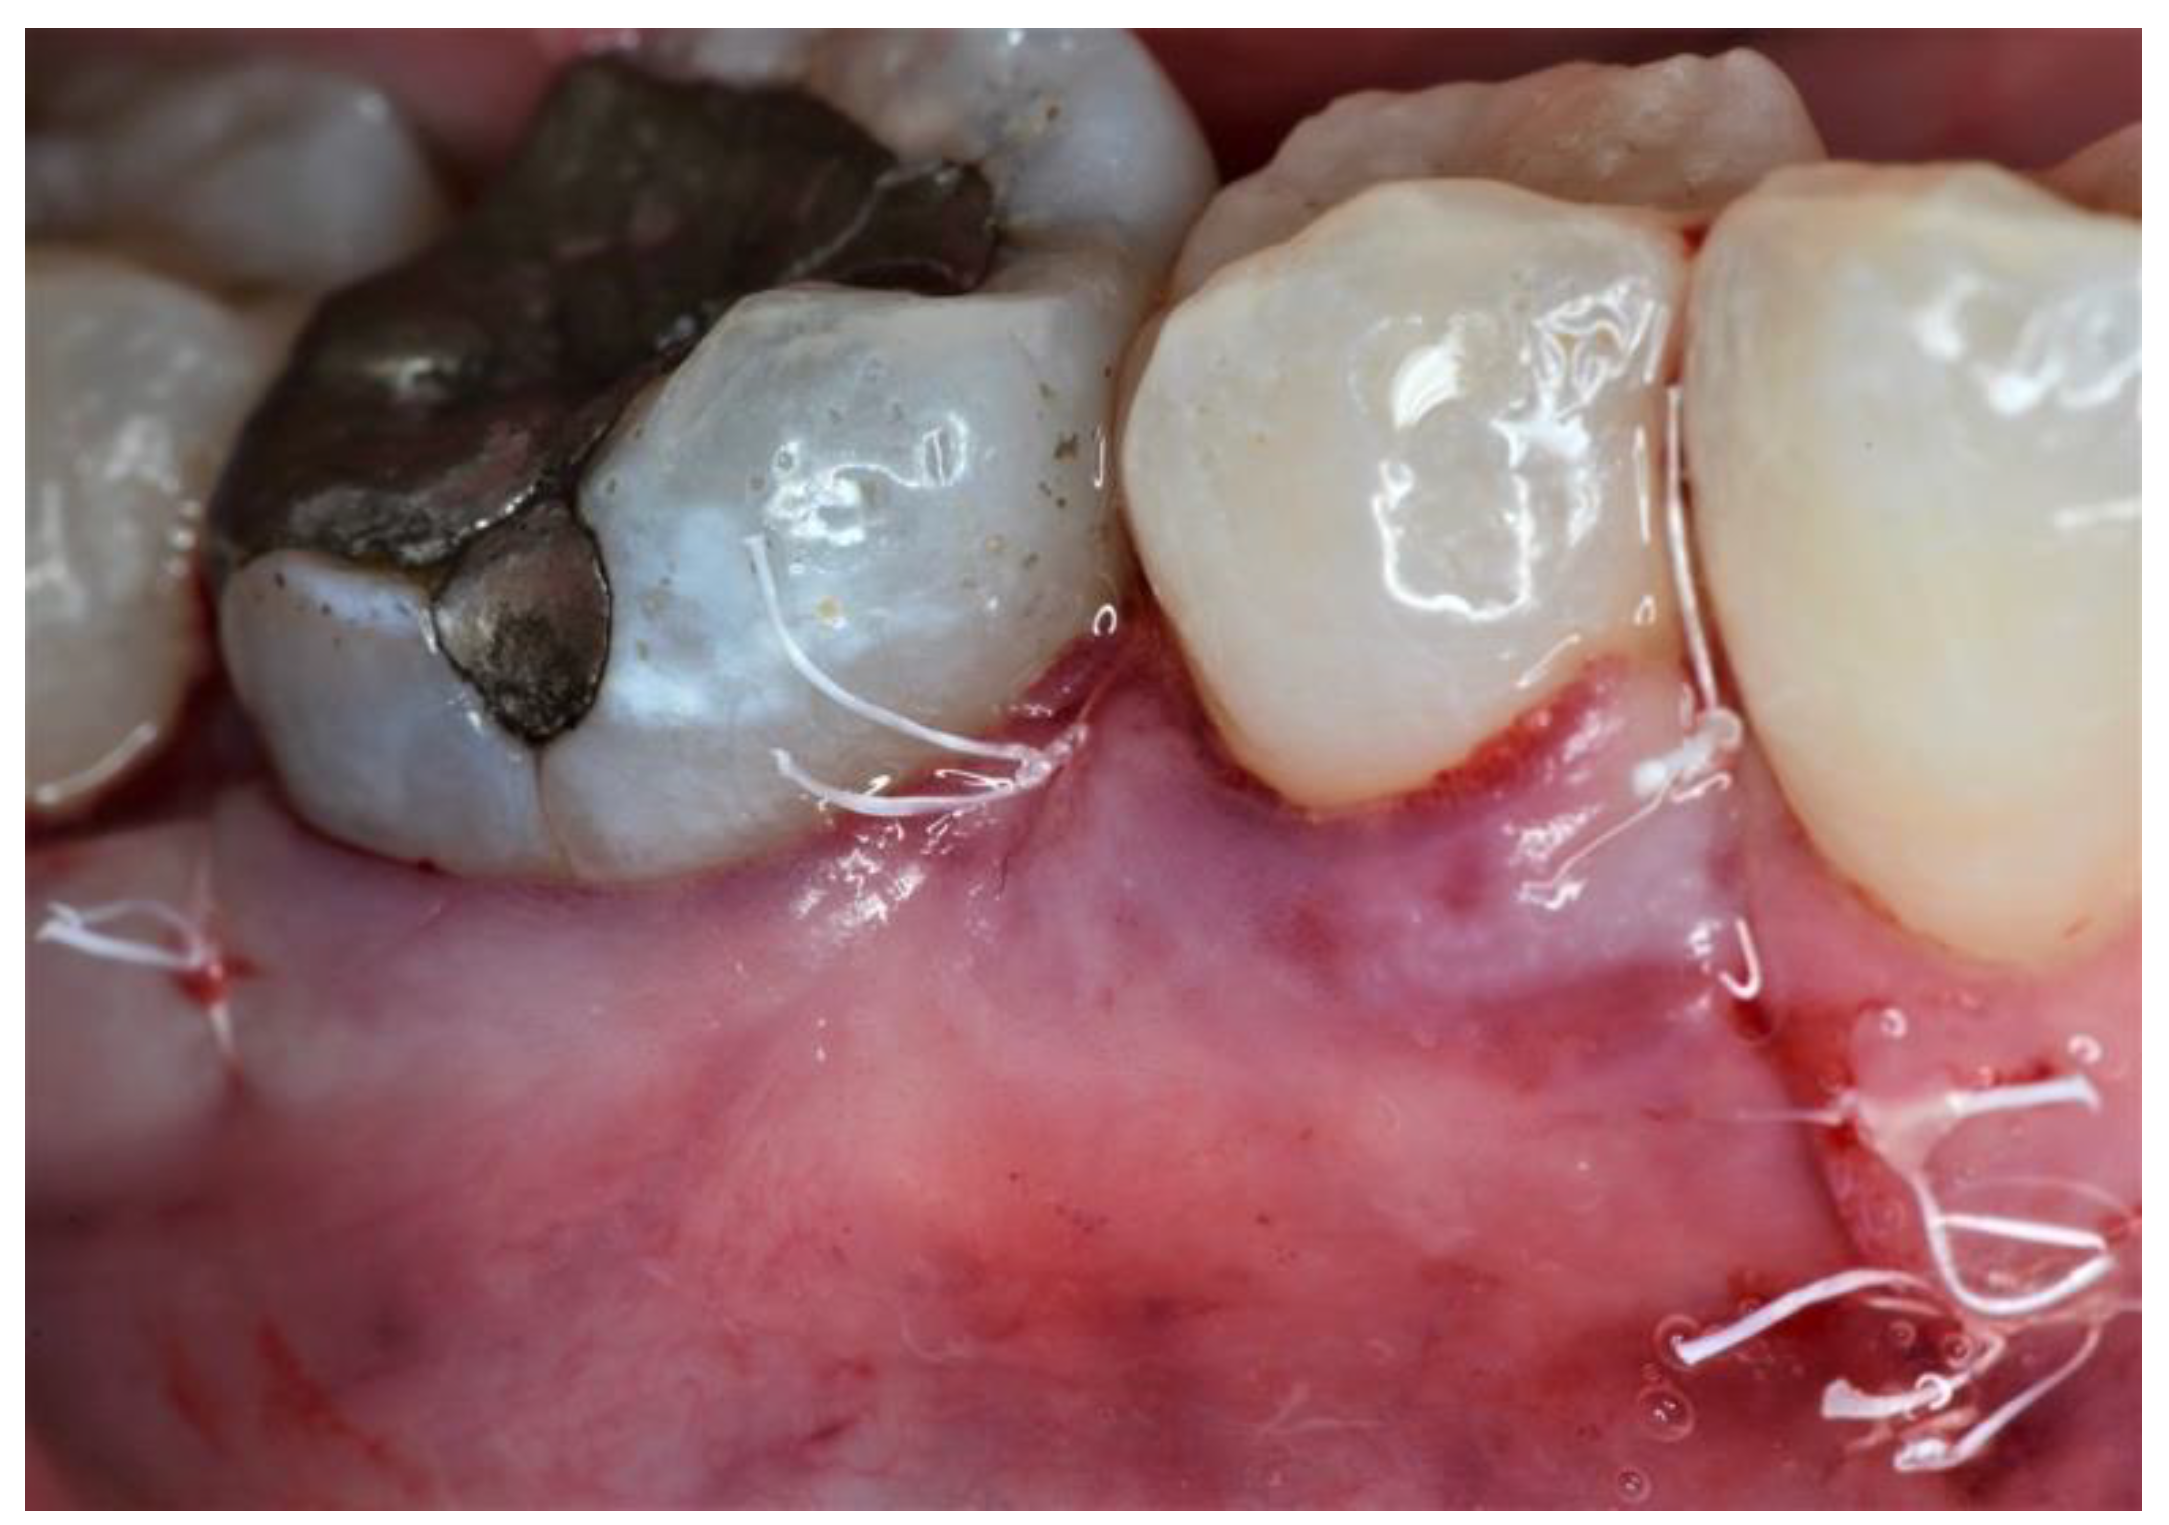

2.3. Therapeutic Intervention